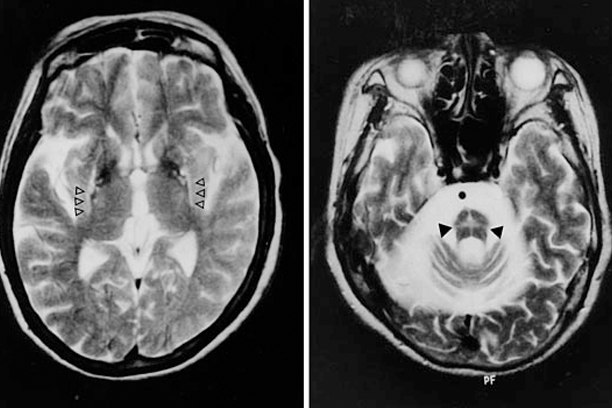

HD may be difficult to diagnose in early stages, particularly with absent or unknown family history. This is because symptoms are complex and vary from patient to patient. At first, symptoms like depression may be more obvious than the chorea. Once chorea is obvious, one can have an evaluation and genetic testing to get a diagnosis. Brain MRI shows shrinkage (atrophy) of certain areas of brain such as caudate nucleus and putamen. Genetic testing for HD confirms the diagnosis.

No single test can diagnose MSA. MSA is usually diagnosed based on clinical symptoms and examination findings. Tests may include MRI brain, uroflowmetry tests, and autonomic function testing (such as testing for blood pressure changes, including the tilt-table test). The diagnostic test for confirmation of MSA is autopsy of brain tissue.